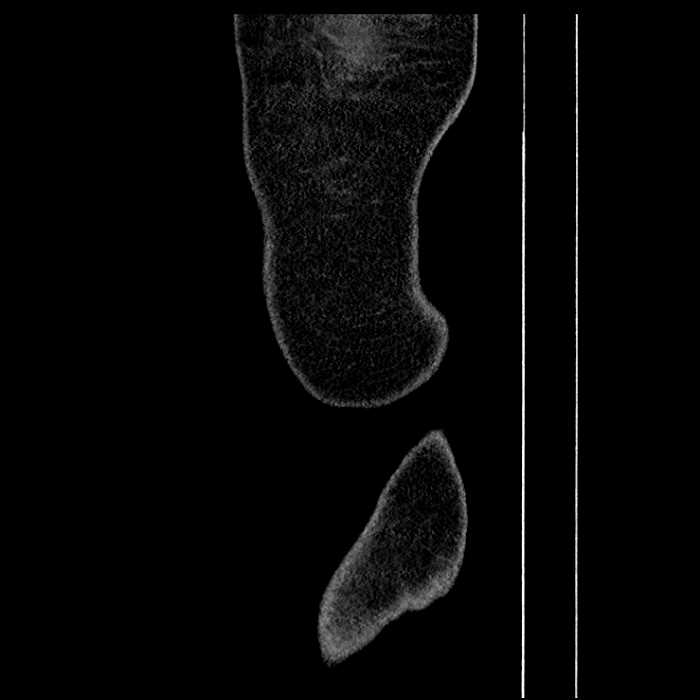

• Incidental splenule

Hepatic abscess showing the double target sign with low density internally surrounded by a thin inner enhancing rim (red arrow) and ill-defined outer low density rim (yellow arrow). Blue arrow indicates an internal septation. Red arrows: additional smaller subcapsular abscesses. Red arrow: focal contained perforation associated with diverticulitis.